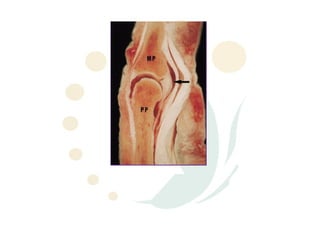

Anatomy - Volar Plate

ď‚§ Floor of joint

ď‚§ Suspended laterally by collateral

ligs.

ď‚§ Distal portion inserts across volar

base of MP (only densely

attached at its lateral margins -

col. lig. insertion)

ď‚§ Thinner centrally & blends with

MP volar periosteum

ď‚§ Central portion tapers proximally

into an areolar sheet & laterally

thickens to form a pair of check

ligaments

ď‚§ Secondary stabilizer against

lateral deviation esp when PIPJ

extended but only when

collaterals torn

Anatomy - VolarPlate ď‚§ Floor of joint ď‚§ Suspended laterally by collateral ligs. ď‚§ Distal portion inserts across volar base of MP (only densely attached at its lateral margins - col. lig. insertion) ď‚§ Thinner centrally & blends with MP volar periosteum ď‚§ Central portion tapers proximally into an areolar sheet & laterally thickens to form a pair of check ligaments ď‚§ Secondary stabilizer against lateral deviation esp when PIPJ extended but only when collaterals torn